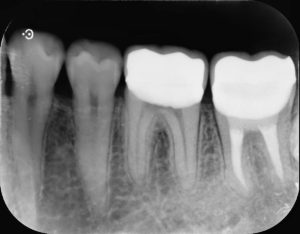

治療後

左下第二大臼歯部に不良補綴物をみとめたため、レントゲン検査を行うと根尖部透過像がみられた。根管内に破折器具がみられたため、破折器具の除去および根管内の感染除去を行った。経過観察後、根尖部透過像の縮小をみとめたため、歯冠修復を行った。

今回の症例では根管内の汚染が強く、破折器具もはじめからしっかり見えたことから超音波切削器具と次亜塩素酸ナトリウム等を用いて除去しました。再度根管充填を行ったあと、病変の縮小をみとめた後に歯冠修復を行いました。

また根管治療後に適合の良い、再感染の起こりにくいジルコニアセラミッククラウンでしっかり再感染を防ぐことが根管治療の予後を左右します。

根管治療とともに歯冠修復物の精度がその歯の予後にとって極めて重要であると言えます。